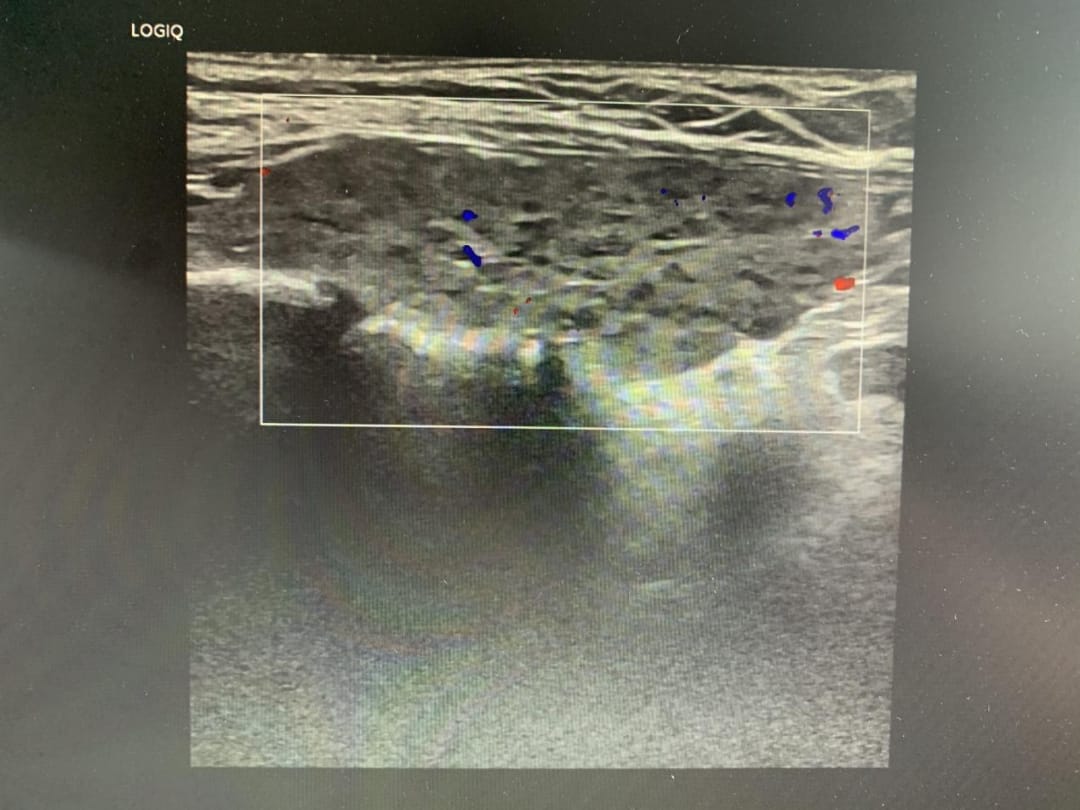

- 甲状腺超声: 显示甲状腺双侧叶实质回声粗糙不均,右侧叶峡部实性结节被评为TI-RADS 4类,左侧叶峡部实性结节为TI-RADS 3类,并伴有双侧颈部多发低回声。

甲状腺右侧叶实质峡部实性结节,边界欠清,其内可见少许血流信号